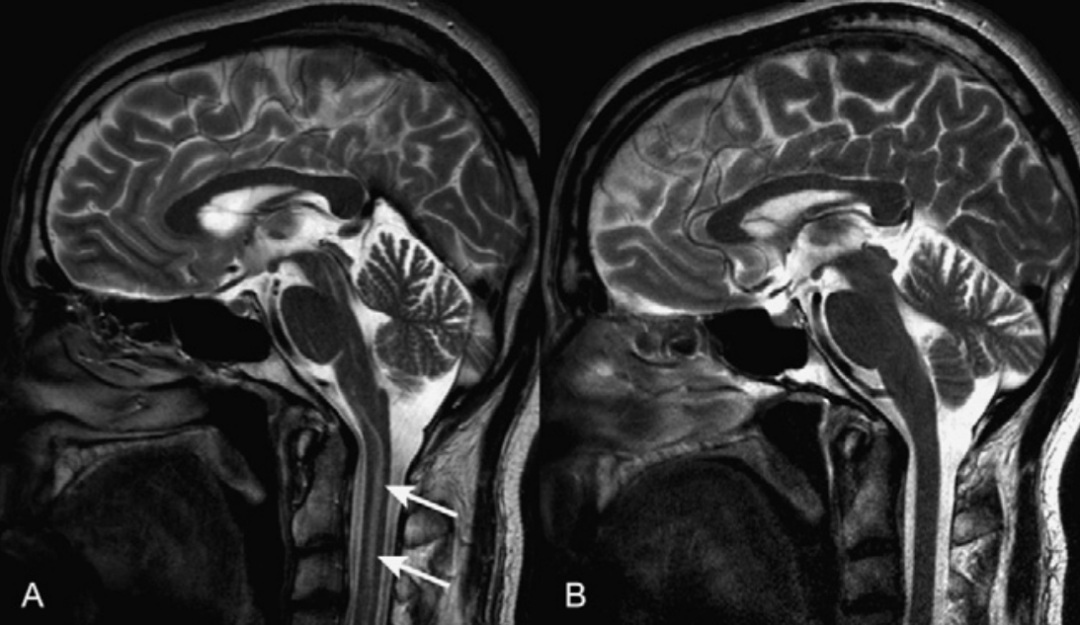

化学位移伪影由于人体中水和脂肪内氢质子进动频率差异所致,常出现在水/脂界面,可能被误认为硬脊膜结构。